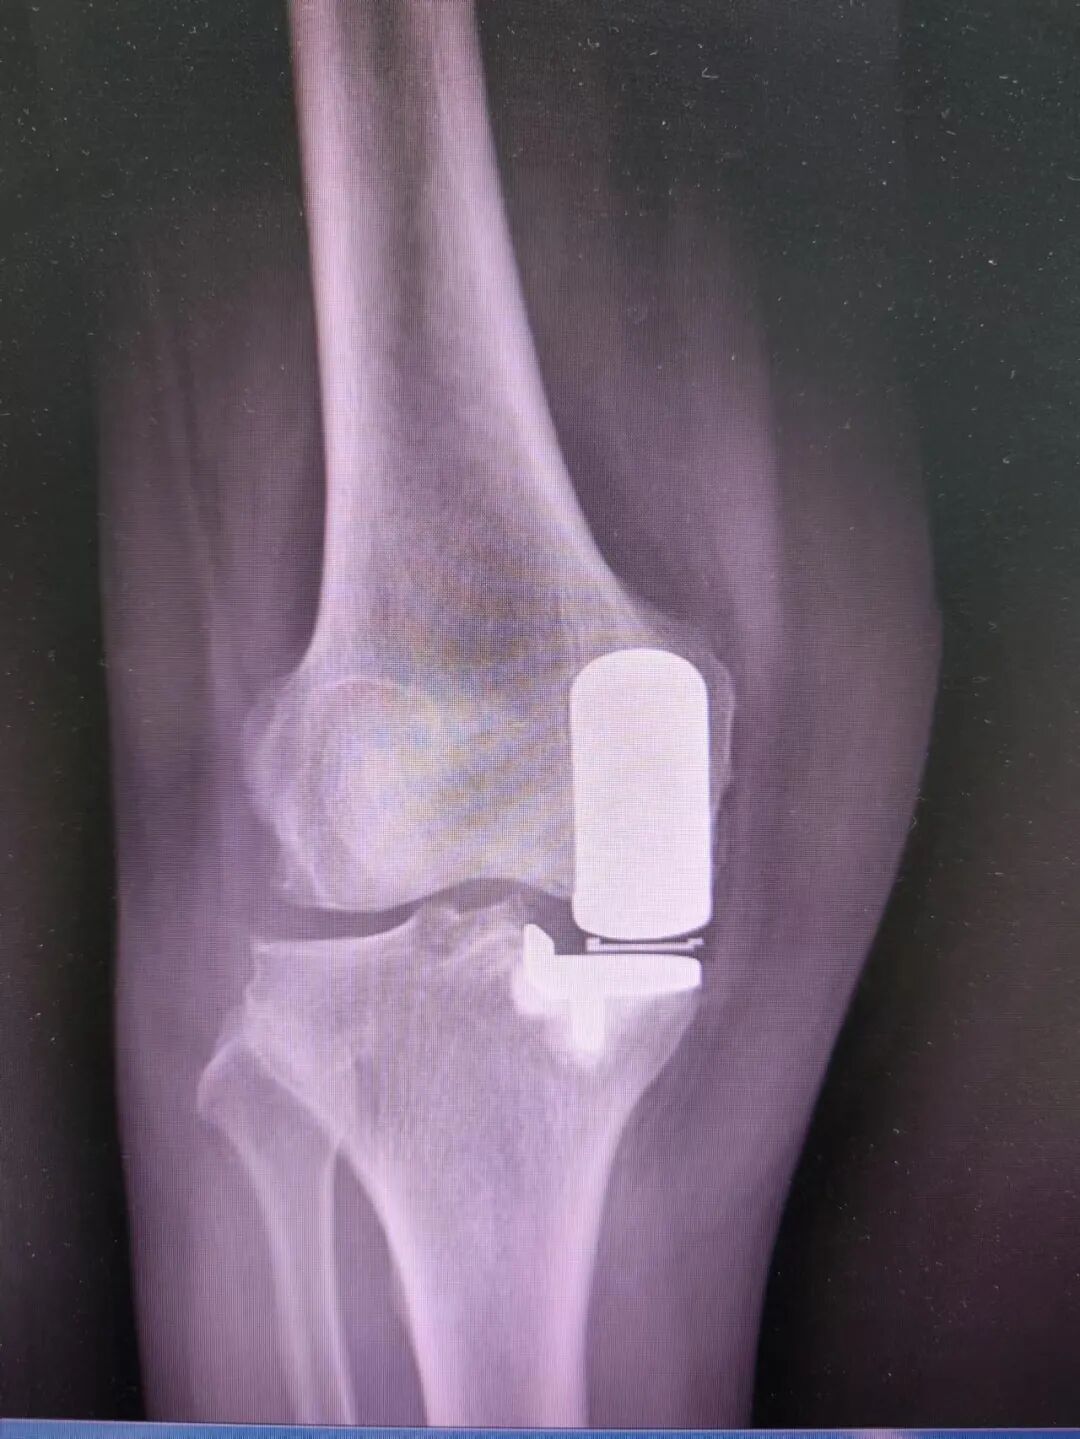

结合患者病史、查体及影像学资料,经科内会诊后决定给吴女士行人工单髁关节置换术,术中所见:

术后第二天扶助行器下地行走。

术后DR。